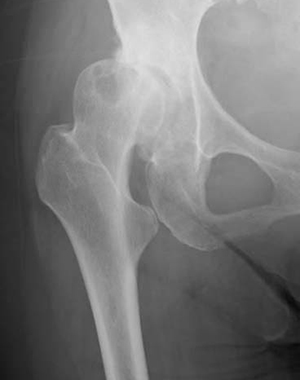

さらには、いくつもの筋肉や靭帯(じんたい)がこの股関節を取り囲むように配置され、股関節を安定化させる働きをしています。また、体幹と下肢をつなぐ太い血管やリンパ管、神経などもそのすぐ近くをとおっています。(写真1、図1)

写真1

【前期】(写真2)

臼蓋形成不全だけがある状態です。

【初期】(写真3)

初期段階の変形性股関節症では、なんらかの原因によって股関節を構成する軟骨の表面が部分的に傷つき、削られます。すると、損傷部位を修復するために白血球などが集まって炎症が起こり、ブラジキニンやプロスタグランジンといった痛みや炎症を引き起こす生理活性物質がつくられます。これらが、関節包や滑膜、靭帯、軟骨下骨(関節軟骨の下部に位置する骨)などにある痛みを感じる神経(侵害受容器)を刺激し、痛みを引き起こすのです(関節軟骨自体には痛みを感じる侵害受容器はありません)。主に、これら滑膜や靭帯などの炎症によって股関節が痛む段階が、変形性股関節症の初期段階です。部分的に傷つき削られているとはいっても、まだ関節軟骨は残っており、寛骨臼にも大腿骨頭にも大きな変形はありません。レントゲン写真では寛骨臼と大腿骨頭のすき間も、部分的に狭くなり始めています。

【進行期】(写真4)

初期段階の変形性股関節症から股関節の状態は次第に悪化していきます。関節軟骨がさらに削られ部分的になくなってしまい、骨と骨とが直に接触してしまう箇所が出ててきます。寛骨臼や大腿骨頭には、骨に小さな変形が起きて「骨棘(こっきょく )」という突起ができ始めていることもあります。骨の内部では骨嚢胞ができ始めて空洞化が進みます。また、軟骨のすり減りによって引き起こされる滑膜や靭帯の炎症のほか、骨の表面にある「骨膜(こつまく)」という痛みを感じる組織も刺激されるので、ほとんどのケースで強い痛みを慢性的に感じるようになります。立ったり歩いたりすることに困難を感じ始めるのもこの頃です。この段階でレントゲン写真を撮ると、寛骨臼と大腿骨頭のすき間が非常に狭くなっているのが判別できます。

【末期】(写真5)

時間とともに股関節の状態はさらに悪化し、末期的な段階にまで達します。関節軟骨はほとんど消えてなくなってしまい、骨と骨が完全にぶつかり合うようになります。関節軟骨には痛みを感じる神経はありませんが、その下にある骨には痛みを感じる神経があるので、こうなると余計に痛みを感じるようになります。さらに、骨同士の接触面には間にクッションの役目を果たす組織が何もないことから、双方がどんどん傷ついて削れ、変形していきます。骨棘も数多く形成され、骨の内部が空洞化する骨嚢胞も多数でき、そのサイズも大きくなります。この段階でレントゲン写真を撮ると、関節のすき間が消失してみえなくなっており、そのために外見からも、両下肢の長さが明らかに異なっているのがわかるようになります(片方の股関節のみに症状がある場合)。この段階でも、患者さんは激しい痛みを感じます。ただ、あまりに長期間治療をせずに痛みを我慢し続けていると、押しつけられた骨と骨とが癒着して固定化され、関節の動きがかなり制限されるようになるため、逆に痛みを感じなくなることもあります。ただしこの場合には、股関節の骨が固まってしまっているわけですから、当然、もはや股関節は正常な働きをせず股関節の動きは悪くなっています。